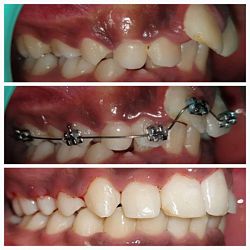

Case No: 25

Malocclusion Type: Skeletal Class III and Dental Class I Malocclusion.

Mechanics: MBT Mechanics.

Treatment: Skeletal Class III Dental Class I Malocclusion with crowding in upper anteriors and anterior crossbite treated Non-surgically.